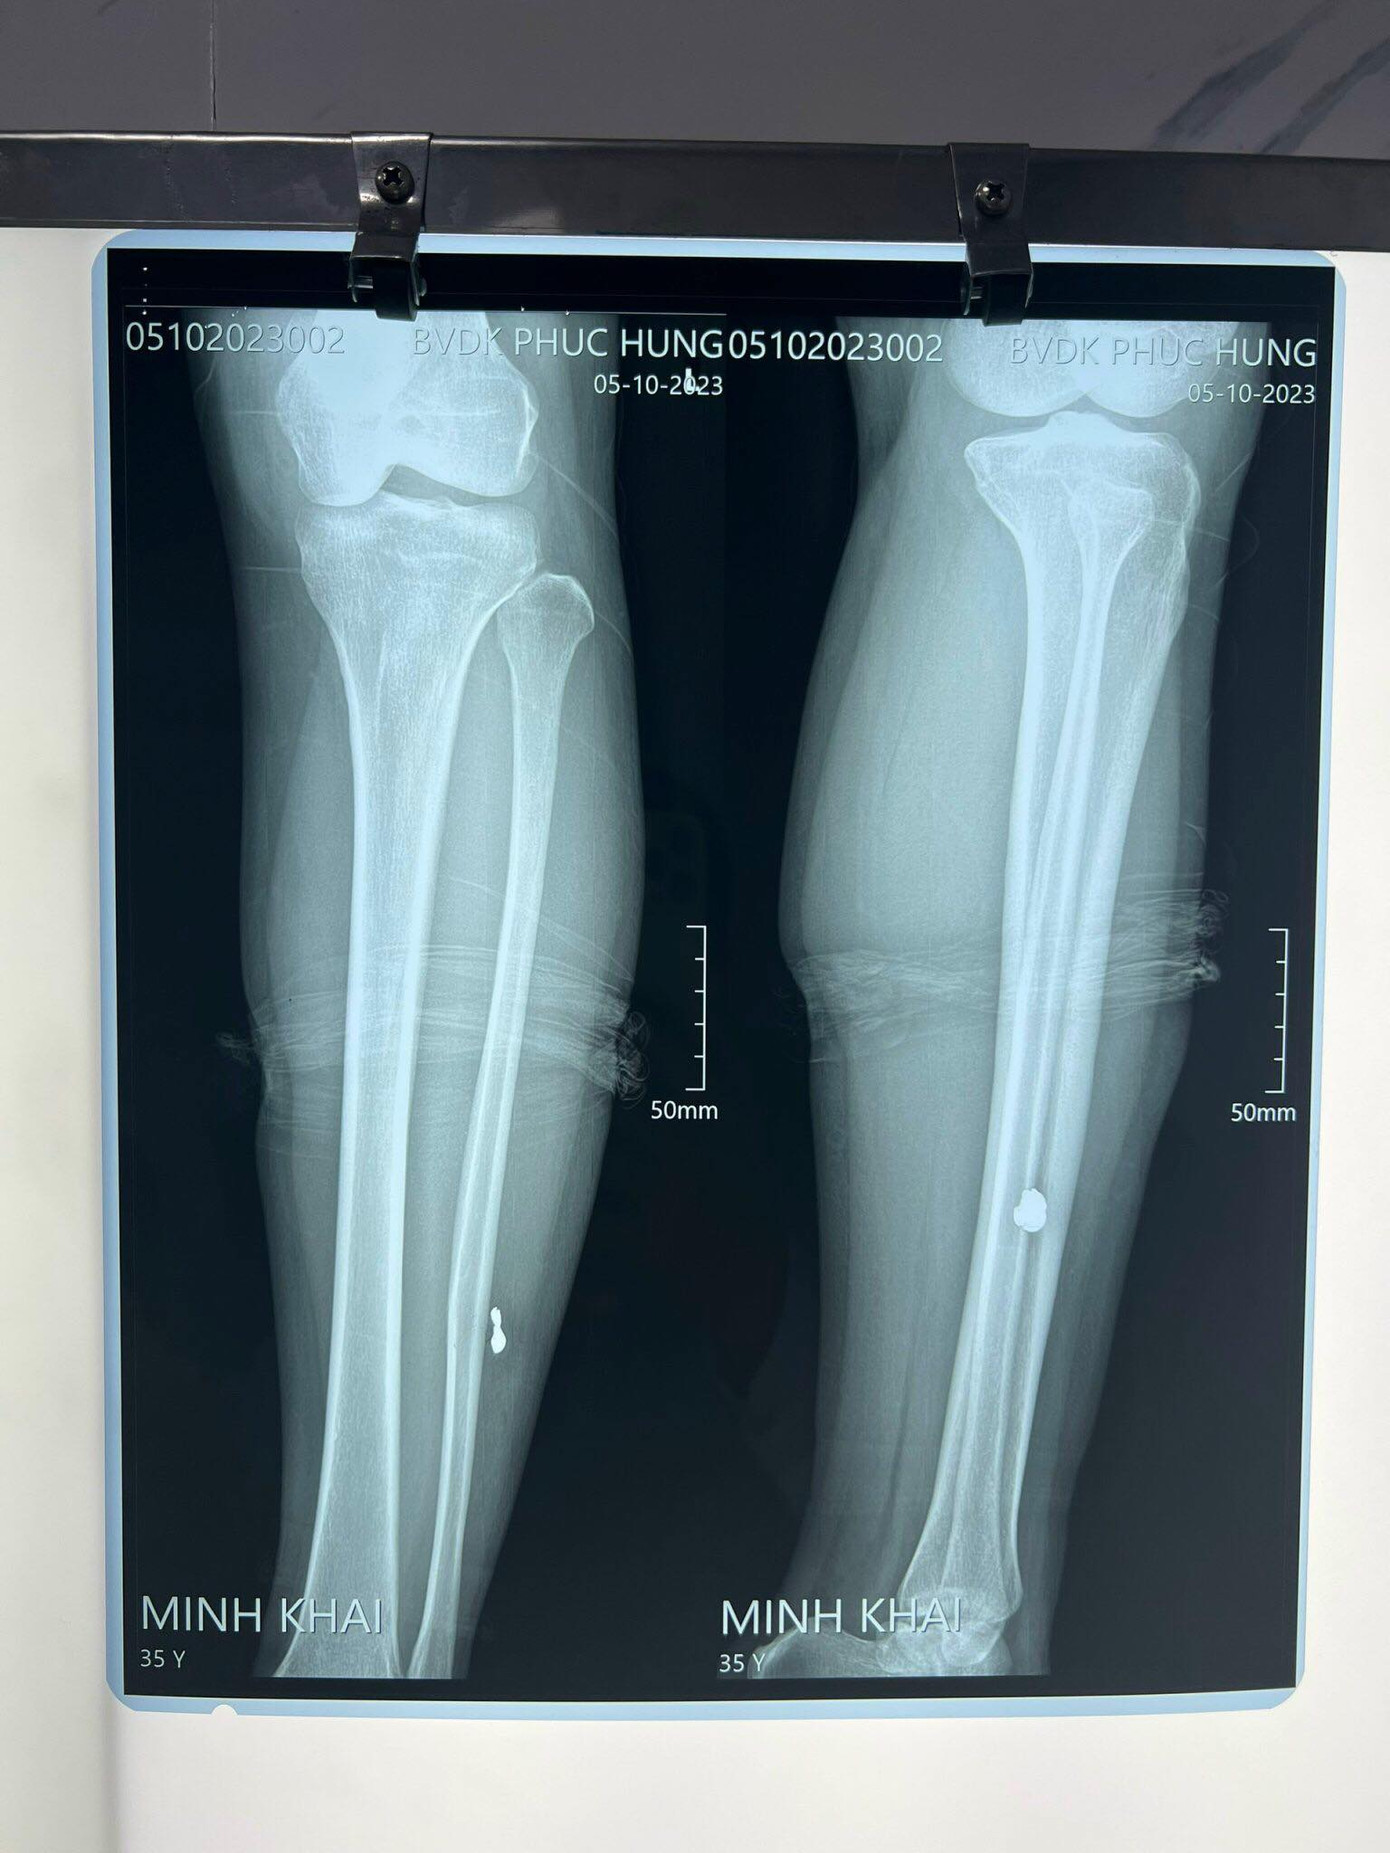

Một số người dân sống gần khu vực này nghe tiếng súng nổ đến hiện trường, nhóm thanh niên trên đã bỏ đi. Hai nạn nhân sau đó được đưa vào Bệnh viện Đa khoa Phúc Hưng để cấp cứu. Kết quả chụp phim cho thấy cả hai người đều có đạn trong đùi và bắp chân.

Đến ngày 5/10, sức khỏe hai lao công đã ổn nhưng tinh thần vẫn còn rất hoang mang. Các y bác sĩ làm các thủ thuật y khoa xác định được những vết đạn ở chân hai nữ lao công và sẽ phẫu thuật để lấy đầu đạn ra khỏi chân.

| Hình ảnh chụp x quang của hai nữ lao công. |

Hiện vẫn chưa thể xác định loại súng hai thanh niên sử dụng bắn hai nữ lao công là súng gì.